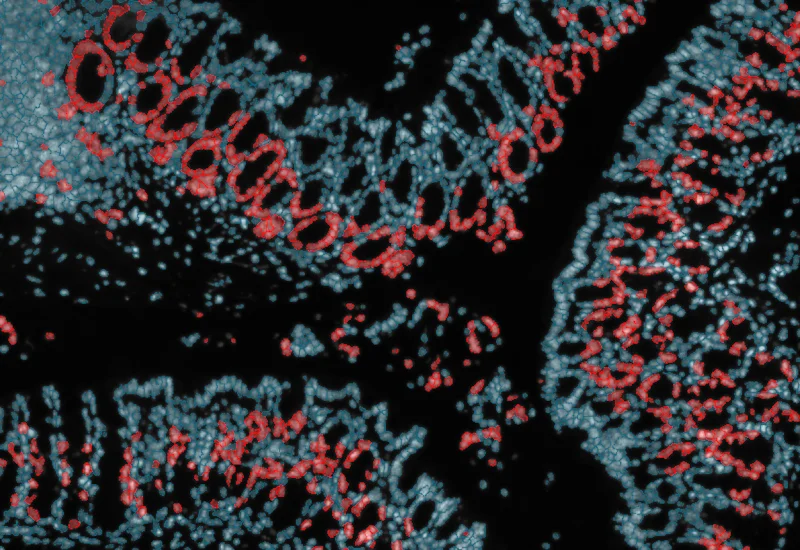

IF Swiss Roll

The IF Swiss Roll App segments tissue into subclasses (e.g., mucosa, follicles, connective tissue), detects nuclei, and identifies phenotypes via IF stains.

mouse, colon, fluorescence, immune cell follicles

The IF Swiss Roll App allows for detection of the swiss roll, and the segmentation into different subclasses (mucosa, immune cell follicles, connective tissue, background). Further it detects nuclei and identifies phenotypes based on specific IF stains. The App outputs area (µm2) of detected tissues/tissue classes, count of total cells as well as in each detected area. Count and % of specific phenotype detected in total as well as in the tissue classes.

Image courtesy of Priv.-Doz.Dr. Martin Schepelmann, Medical University of Vienna

Original Image